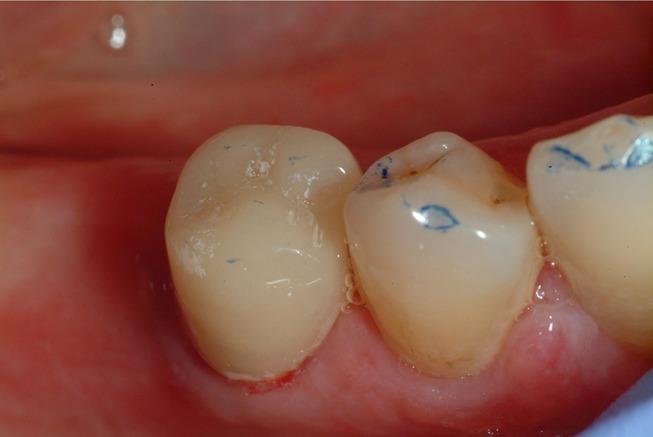

In the reported case an intraoral scan was used to mill a post and core restoration on an endodontically treated inferior premolar; this operative protocol was based on previous in vitro experiments that confirmed the ability of 3shape Trios scanner to read post-space up to 9 mm in depth.

RESULTS

The digital technique allows us to convert the concave surface of the root canal into the convex surface of the post, and realize an anatomical post and core that improves the biomechanics of the endodontically treated tooth reducing the possibility of root fractures.

在本报告病例中,使用口内扫描仪为一颗根管治疗后的下颌前磨牙制作桩核修复体;该手术方案基于先前的体外实验,该实验证实了3shape Trios扫描仪能够读取深度达9毫米的桩道空间。

结果

数字技术使我们能够将根管的凹面转化为桩的凸面,并制作出解剖形态的桩核,改善根管治疗后牙齿的生物力学性能,降低牙根折断的可能性。